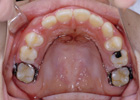

2.ブラケット:

歯に装置を接着して、ワイヤーを用いて歯並びを治します。

<表側矯正装置>